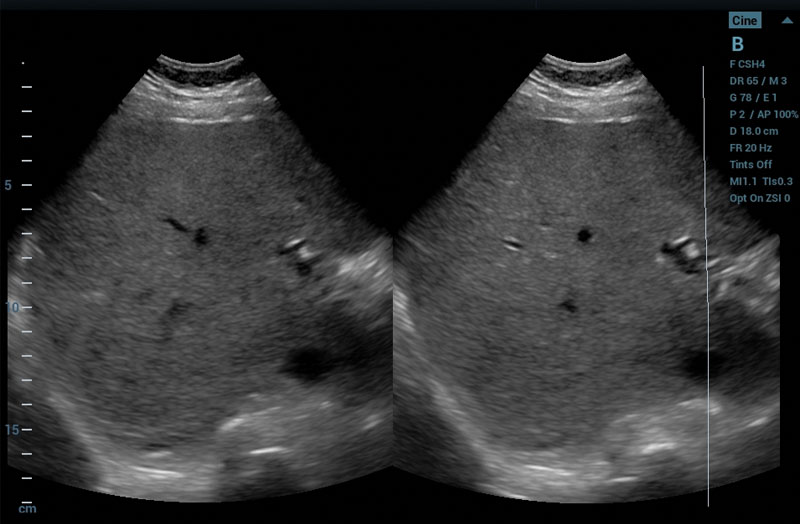

The ZS3 Ultrasound System Diamond Edition 2.0 is the ultimate imaging platform combining premium performance and mobility for today’s demanding ultrasound environments. Equipped with next generation ZONE Sonography® Technology+ (ZST+), the ZS3 System takes image clarity to new heights across a broad spectrum of body types from pediatric to bariatric. With every pixel in focus to imaging depths up to 40cm, the ZS3 System delivers unsurpassed image quality for the widest range of clinical applications.

The ZS3 Radiology Ultrasound System is a smaller, lightweight system that glides into place. An extended battery combined with rapid transition times results in increased exam efficiency and patient throughput.